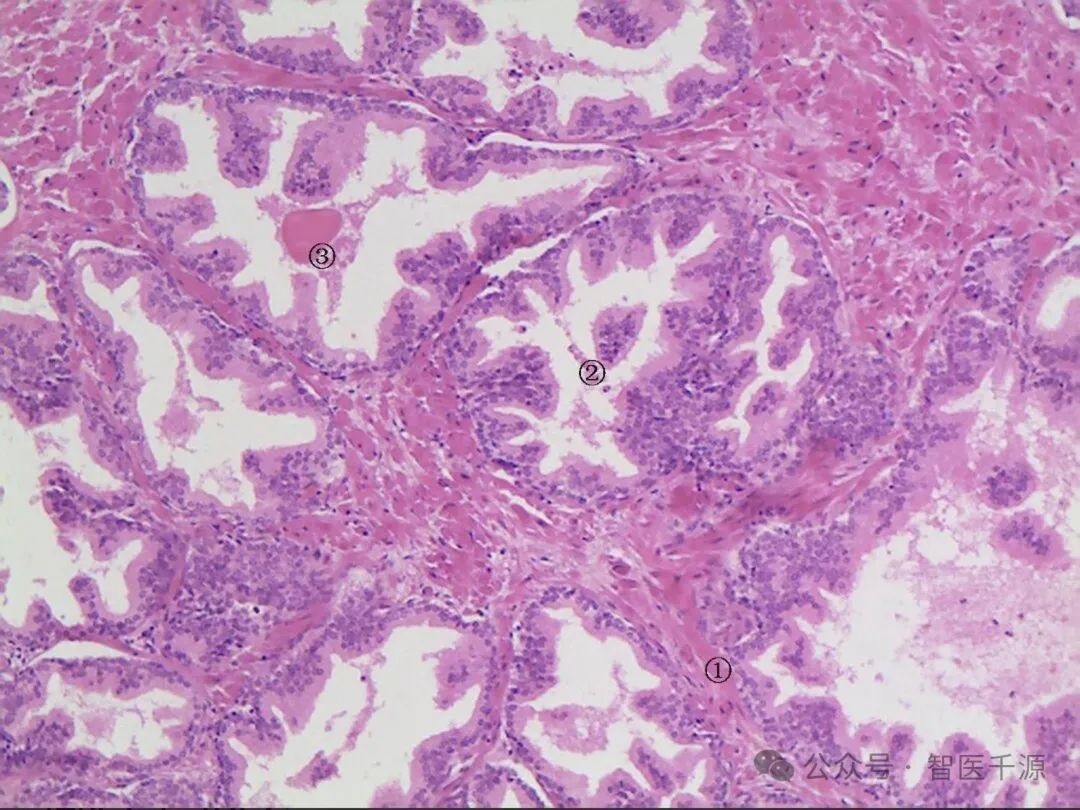

这张病理切片显示了肺部组织的显微镜图像,使用了H&E染色。图中可以看到肺泡结构,其中一些肺泡内有细胞浸润,这些细胞呈现出不规则的形状和大小,这是肿瘤细胞的特征。这些肿瘤细胞的核较大,染色质密集,核仁清晰可见,这些都是肿瘤细胞的典型特征。图中还标记了两个区域,一个是肺泡内的肿瘤细胞浸润,另一个是肺泡壁的肿瘤细胞浸润。这些特征表明存在肺部的肿瘤性病变,可能是肺癌。

原片如下: